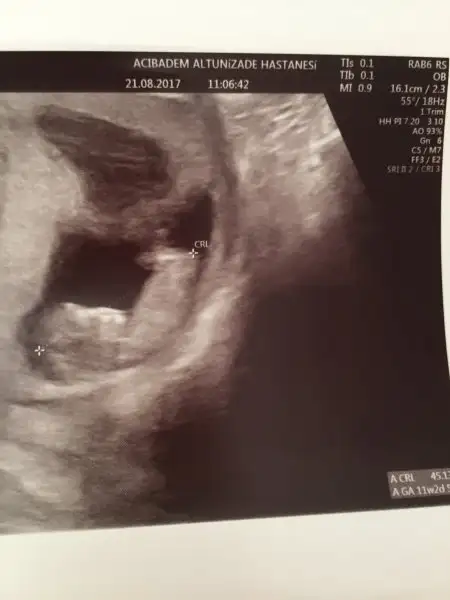

Kızlar merhaba biz 11 haftalık olduk :) doktor cinsiyetle ilgili bir şey demedi buradan ultrasona bakıp tahmin edenler yardımcı olabilir mi acaba? Foto yüklüyorum bu arada ikizler ayrı ayrı foto atıcam

Eklentiler

• IMG_6024.webp

7 KB · Görüntüleme: 86

• IMG_6027.webp

10,6 KB · Görüntüleme: 85